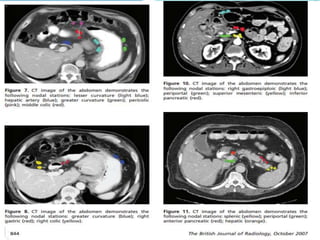

Simulation film for T3 antral tumor with two of five peritumoral lymph

nodes metastatically involved

Editor's Notes

• #52 Simulation film for T3 antral tumor with two of five peritumoral lymph nodes metastatically involved (radical subtotal gastrectomy with D1 node dissection). Simulation film identifies areas at risk for recurrence, including preoperative gastric/tumor bed (defined by preoperative computed tomography [CT] scan), anastomotic sites and gastric stump (staple line seen on precontrast simulation films and marked on postintravenous pyelogram/postcontrast film), and regional lymphatics (celiac, porta hepatis, superior mesenteric artery, and splenic nodes identified on CT, and pancreaticoduodenal nodes lie in C-loop of duodenum identified by preoperative CT). The right kidney is spared for approximately three-fourths of its volume, whereas the left kidney has about one-third of its volume blocked